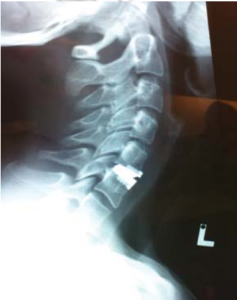

Lateral cervical spine flexional and extension x-rays show good movement of the cervical spine, this is important if we are planning to insert an artificial disc.

We decided to approach this problem via an anterior cervical disectomy ad replace the damaged discs with artificial ones. The advantage to Mr C is that he would not need to wear a cervical brace post op and no risk of increased adjacent disc disease.

Transverse incision is used in this case. It lends itself to healing very nicely with minimal scarring. Once the damaged and prolapsed disc was removed, the endplates were prepared, and the artificial disc inserted. This implant does not require much drilling and is, therefore, safer.